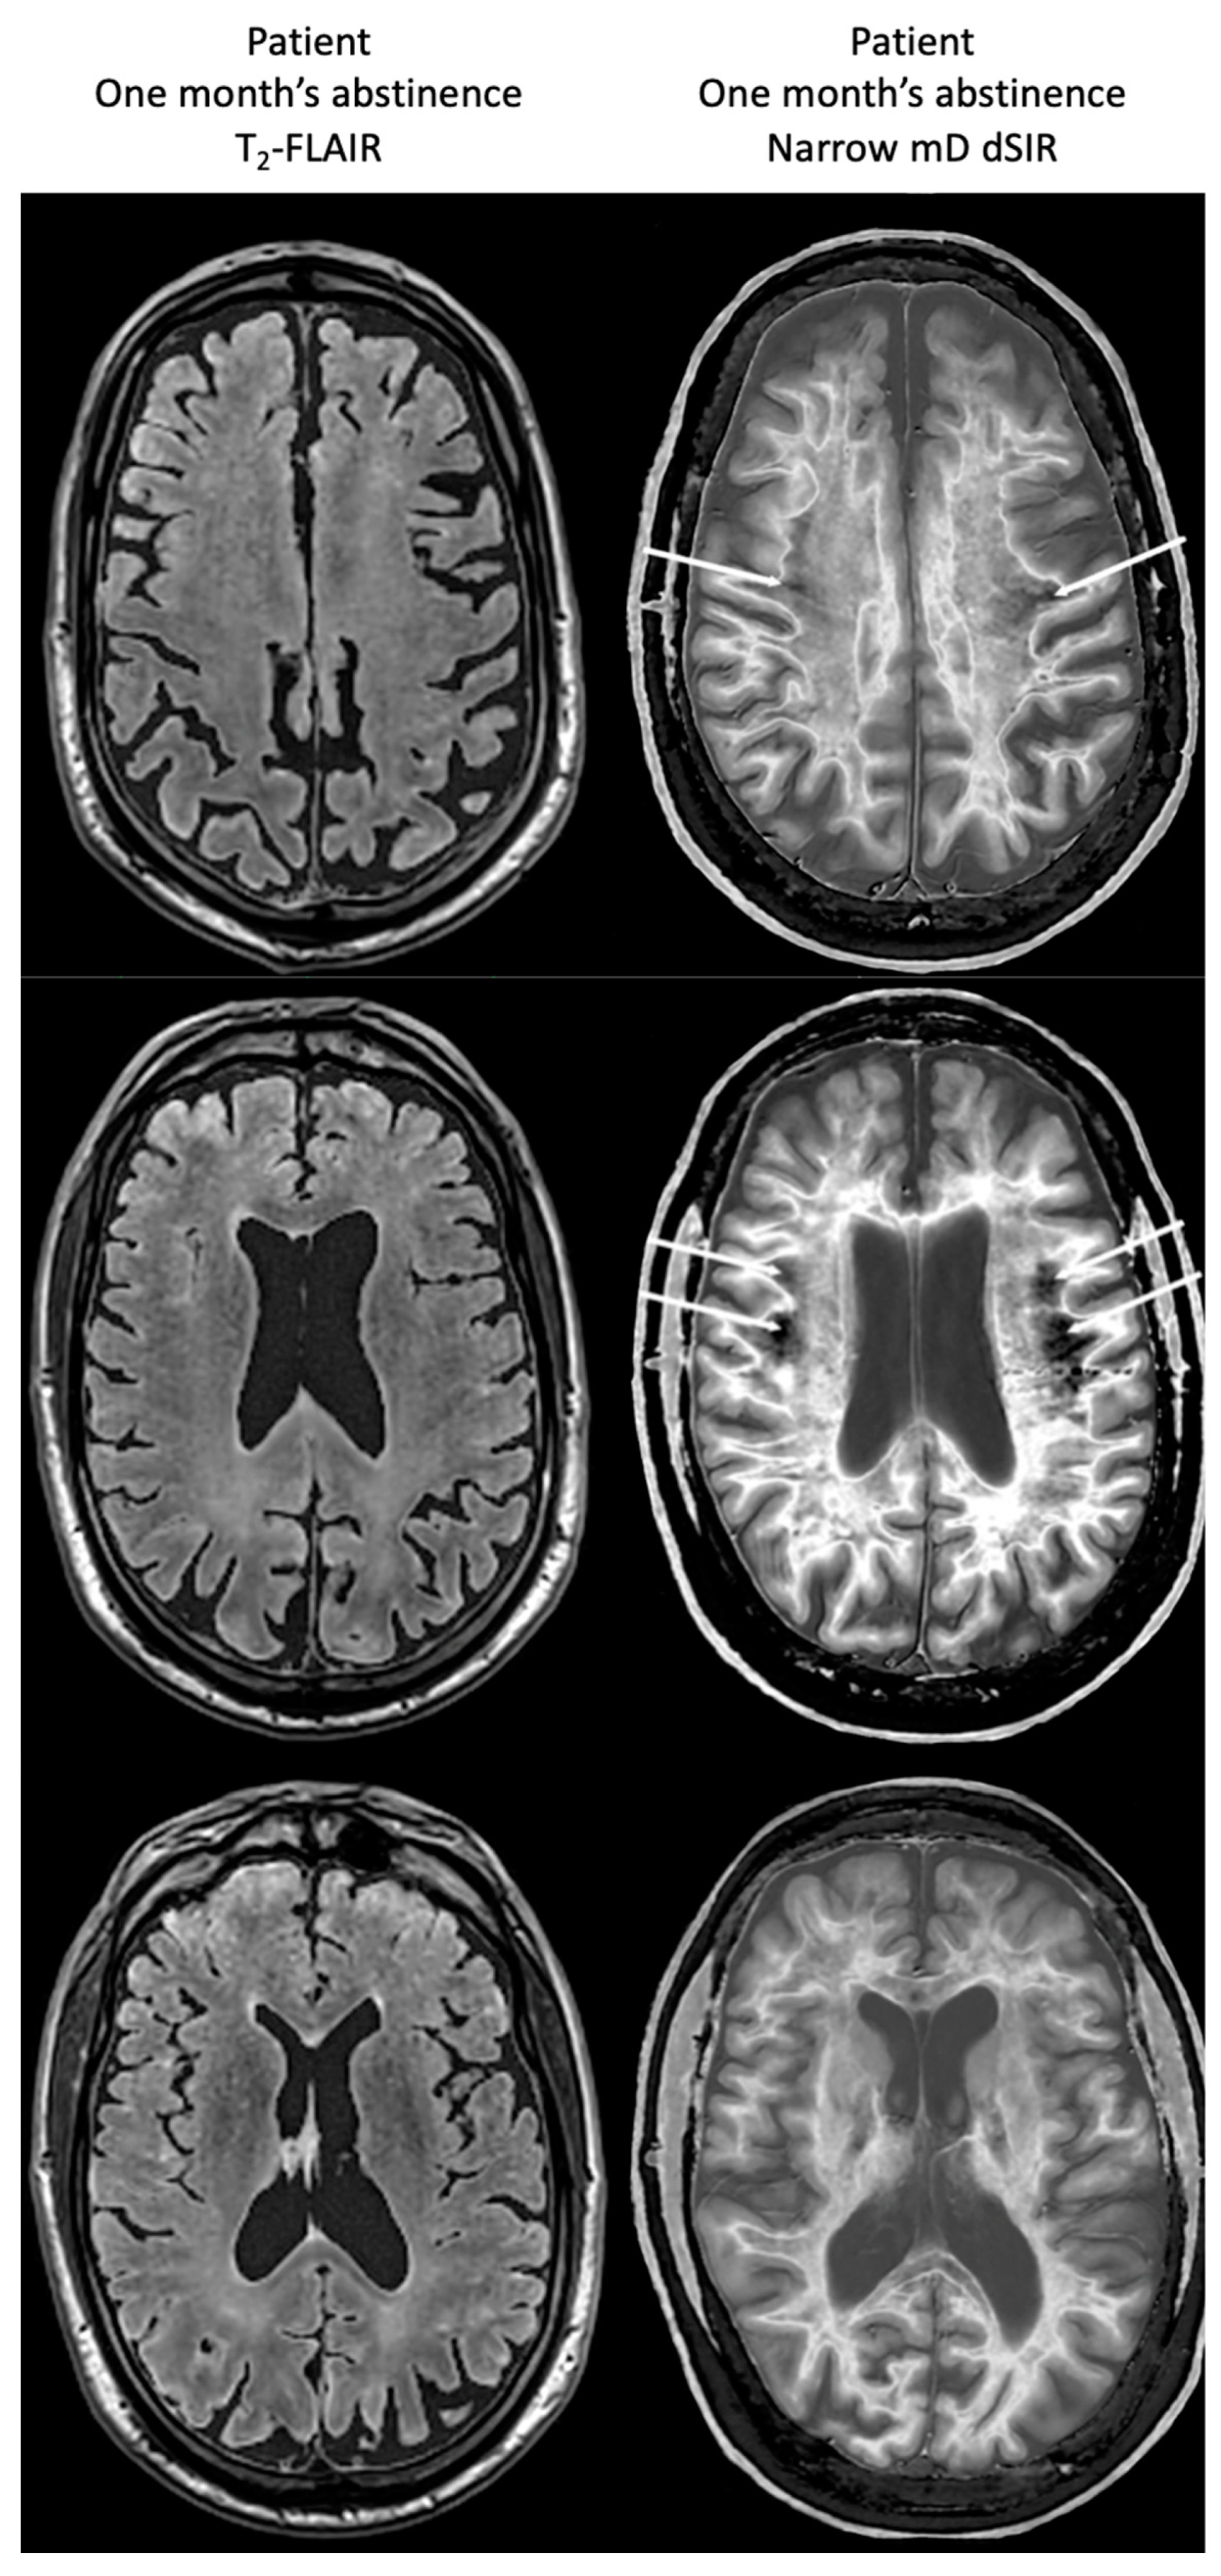

Figure 17, left column shows narrow mD dSIR images from the 50-year-old normal control (left column) and from the patient at his initial MR examination after one month’s abstinence. The normal control shows a very low signal (dark) appearance in most of his white matter. There is an intermediate signal and higher signal in and around the corticospinal tracts (whiteout sign grade 1). In the right column, the patient’s white matter shows extensive areas of high signal with only small areas of more normal lower signal white matter present in the periphery (white arrows) (whiteout sign grade 4).

Figure 17.

A 50-year-old normal control (left column) and Case 1, a 51-year-old with methamphetamine use disorder (right column). 2D dSIR narrow mD images are shown. The narrow mD dSIR images in the normal control show most white matter as very low signal intensity (dark) with a mid gray and lighter appearance in and around the corticospinal tracts, i.e., whiteout sign grade 1. The narrow mD dSIR images in the patient show widespread high signal changes in white matter with only small areas of normal dark white matter at the periphery of the white matter (white arrows). The features are consistent with a whiteout sign grade 4. Normal high signal boundaries are seen between white matter and gray matter on the dSIR images in the control and the patient, but are less obvious in the patient because of the high signal in his abnormal white matter.

There is a dramatic difference between normal white matter on the left which is black and abnormal white matter on the right which is white (apart from small spared or relatively spared areas).

Figure 18 compares T2-FLAIR images (left column) with matched narrow mD dSIR images (right column) in Case 1 at the time of his first examination. No abnormality is seen in the white matter on the T2-FLAIR images (left column) but extensive high signal abnormalities are seen in white matter on the narrow mD dSIR images. Small areas of more normal white matter with a low signal appearance are shown by the white arrows (right column). These are features of a whiteout sign grade 4.

Figure 18.

Case 1 patient with methamphetamine use disorder. Comparison of T2-FLAIR and narrow mD dSIR images. No abnormality is seen on the T2-FLAIR images (left column) but there are extensive areas of higher signal in approximately 90% of the white matter (right column). Only small areas of normal low signal are seen in the white matter (white arrows) (right column). The appearances on the dSIR images are consistent with a whiteout sign grade 4.